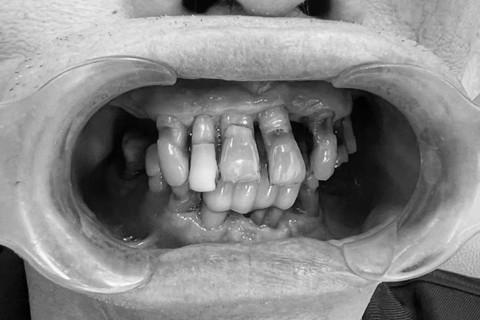

Mất răng gây ảnh thưởng thẩm mỹ và ăn nhai nghiêm trọng. Nhiều người có tâm lý chủ quan khi mất một hoặc vài chiếc răng, đặc biệt ở vị trí khuất như răng hàm. Tuy nhiên, chỉ sau 3–6 tháng không phục hình, xương hàm tại vùng mất răng bắt đầu tiêu biến. Hậu quả kéo theo là các răng kế cận xô lệch, làm lệch khớp cắn và gây đau khớp thái dương hàm. Về lâu dài, khuôn mặt bị hóp má, lão hóa sớm và khả năng ăn nhai suy giảm nghiêm trọng.

Cận cảnh tình trạng mất răng gây xô lệch các răng còn lại trên cung hàm.